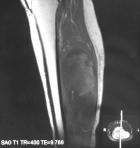

D.V. – 66 year old white female with four month history of left calf mass she first noticed after car ride from Florida. Mass is non-tender, extremity NVI.

Zoom image: Radiological image Radiological image.